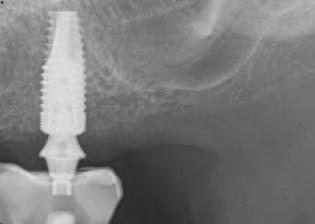

O pac entă de 61 an s-a prezentat la Per odont cs/Per odontal Prosthes s Cl n c d n cadrul Un vers ty of Pennsylvan a School of Dental Med cne dor nd în pr nc pal să a bă „d nț f xaț ” în locul protezelor mob le ex stente (f g. 1). După f nal zarea unu examen stomatolog c cupr nzător, nclus v exam narea extra- ș ntraorală, evaluarea pr n tomograf e computer zată cu fasc cul con c (CBCT), fotograf erea dentară ș întocm rea f șelor dentare, s-a creat un plan pentru real zarea une reab l tăr full-mouth folos nd mplantur ș proteze dentare f xe. Pac enta purta proteze totale moble retenț onate pe m n - mplantur atât la mand bulă, cât ș la max lar. În t mpul evaluăr n ț ale, ea ș -a expr mat preocupăr le legate de estet ca restaurăr lor ex stente în ceea ce pr vește expunerea g ng vală ș

1. Imaginea intraorală a protezelor existente retenționate de miniimplanturi la prezentarea inițială.

2. Pacienta prezenta expunerea excesivă a componentei gingivale din protezele existente.

3. Situația pretratament mandibulară edentată cu cele patru mini-implanturi existente.